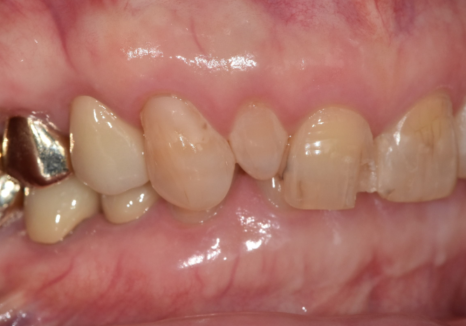

이 환자분도 교정보다는

작은 앞니의 크기를 주변 치아와 맞추고,

앞니 사이 벌어짐과 깨지는 레진 문제를

함께 해결하는 방향이 필요했습니다.

그래서 앞니 라미네이트 치료를

계획했습니다.

이런 과개교합은 라미네이트 치료를 진행할 때

파절 가능성을 최대한 줄이는 것이 가장 중요합니다.

그래서 치아를 많이 깎기보다는

필요한 만큼만 최소한으로 삭제하고,

그 안에서 라미네이트가

안정적으로 자리 잡을 수 있는 공간을 확보하는 것이 핵심입니다.